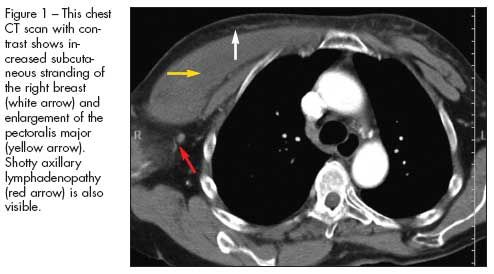

The CT scan of the chest shows increased subcutaneous stranding of the right breast and enlargement of the pectoralis major, with shotty axillary lymphadenopathy (Figure 1). The MRI scan demonstrates myositis of the right pectoralis with an 11 x 2-cm area of lack of enhancement, which is consistent with either necrosis or abscess within the muscle (Figure 2).

Cellulitis (choice C) can be eliminated on the basis of this patient’s history. This superficial infection of the skin with some extension into the subcutaneous tissues The CT scan of the chest shows increased subcutaneous stranding of the right breast and enlargement of the pectoralis major, with shotty axillary lymphadenopathy (Figure 1). The MRI scan demonstrates myositis of the right pectoralis with an 11 x 2-cm area of lack of enhancement, which is consistent with either necrosis or abscess within the muscle (Figure 2).